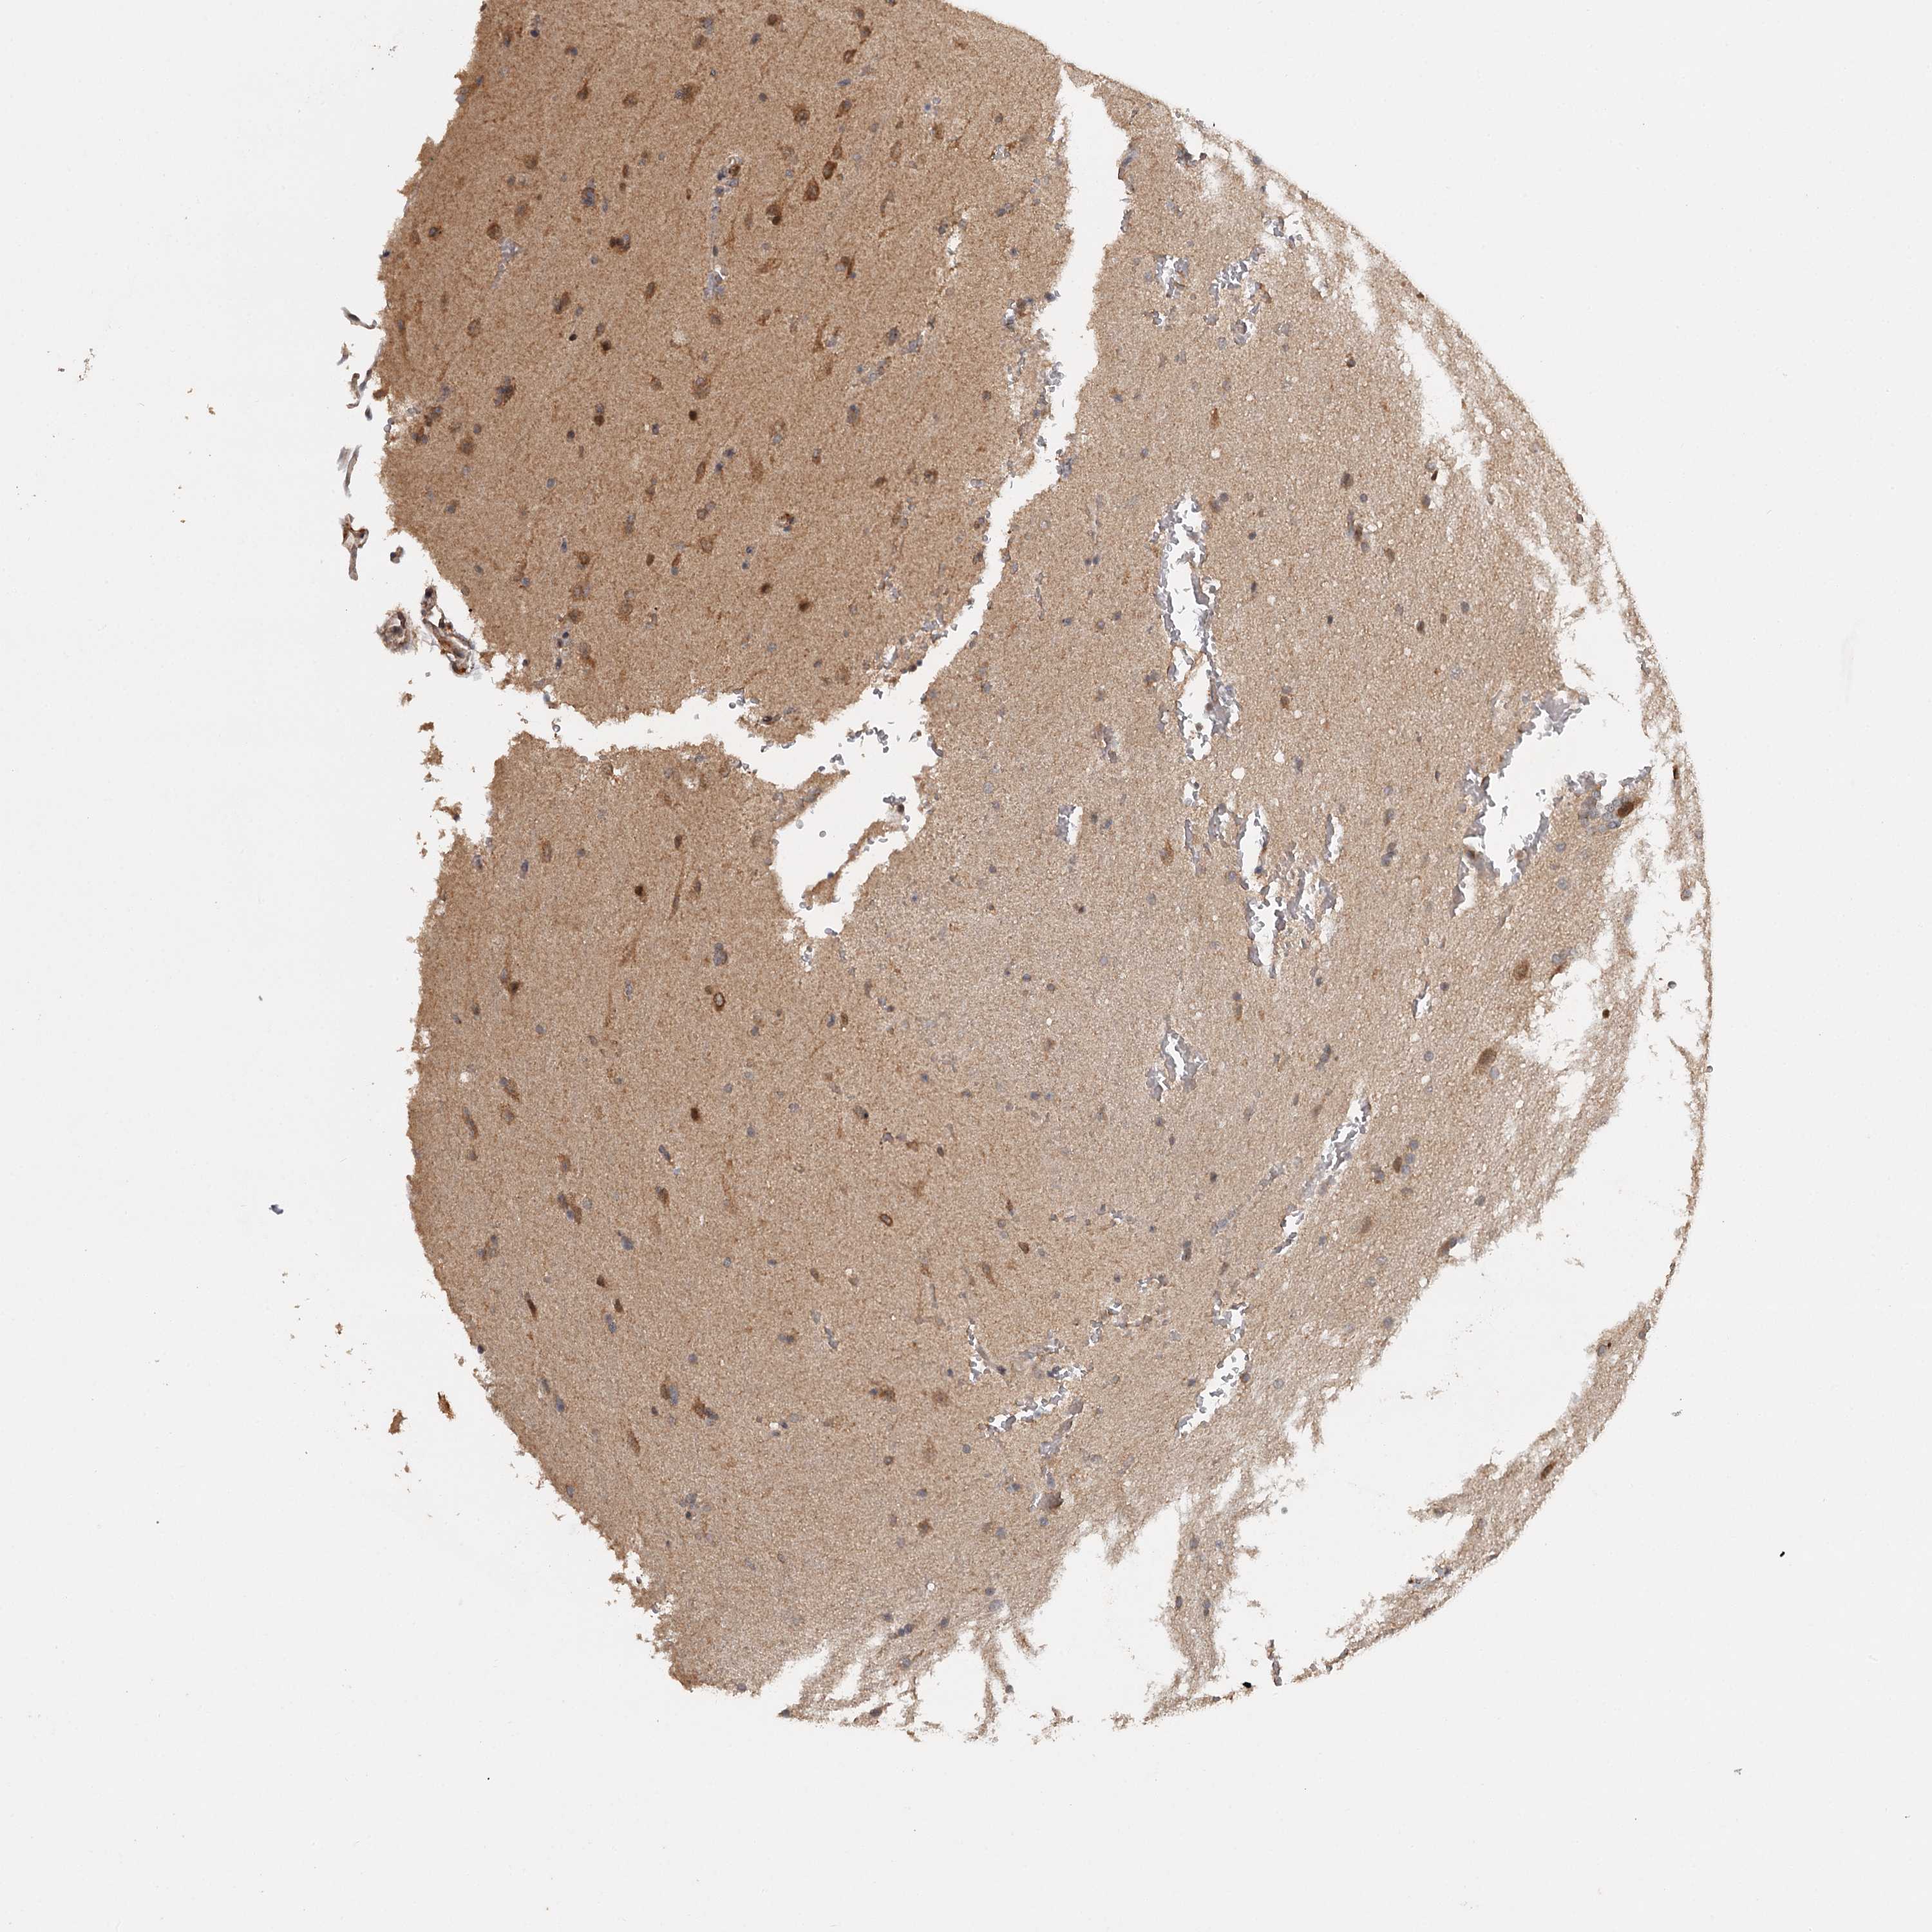

GLIOMA - Protein expressioni

A mouse-over function shows sample information and annotation data. Click on an image to view it in a full screen mode. Samples can be filtered based on level of antibody staining by selecting one or several of the following categories: high, medium, low and not detected. The assay and annotation is described here.

Note that samples used for immunohistochemistry by the Human Protein Atlas do not correspond to samples in the TCGA dataset.

Antibody stainingi

Antibody staining in the annotated cell types in the current human tissue is reported as not detected, low, medium, or high, based on conventional immunohistochemistry profiling in selected tissues. This score is based on the combination of the staining intensity and fraction of stained cells.

Each image is clickable and will lead to virtual microscopy that enables deeper exploration of all samples and also displays staining intensity scores, fraction scores and subcellular localization as well as patient and tissue information for each sample.

Antibody HPA039106

Staining

High

Medium

Low

Not detected

Intensity

Strong

Moderate

Weak

Negative

Quantity

>75%

75%-25%

<25%

None

Location

Nuclear

Cytoplasmic/membranous

Cytoplasmic/membranous,nuclear

Glioma, malignant, High grade

Glioma, malignant, Low grade

Glioblastoma, NOS